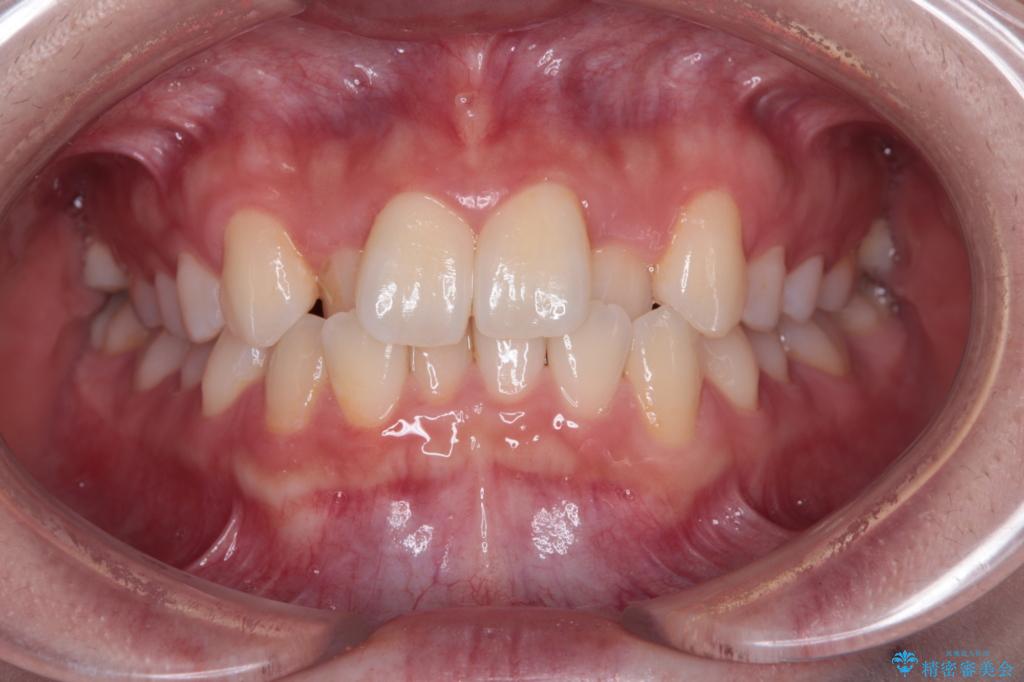

- 上顎前歯のクロスバイトを気にして来院された患者様です。

装置の外見を気にしていましたが、短期間で治療を終えることができるだろうと伝えると、安価であるメタルブラケットを選択されました。

想定通り、1年強で綺麗に仕上げることができました。